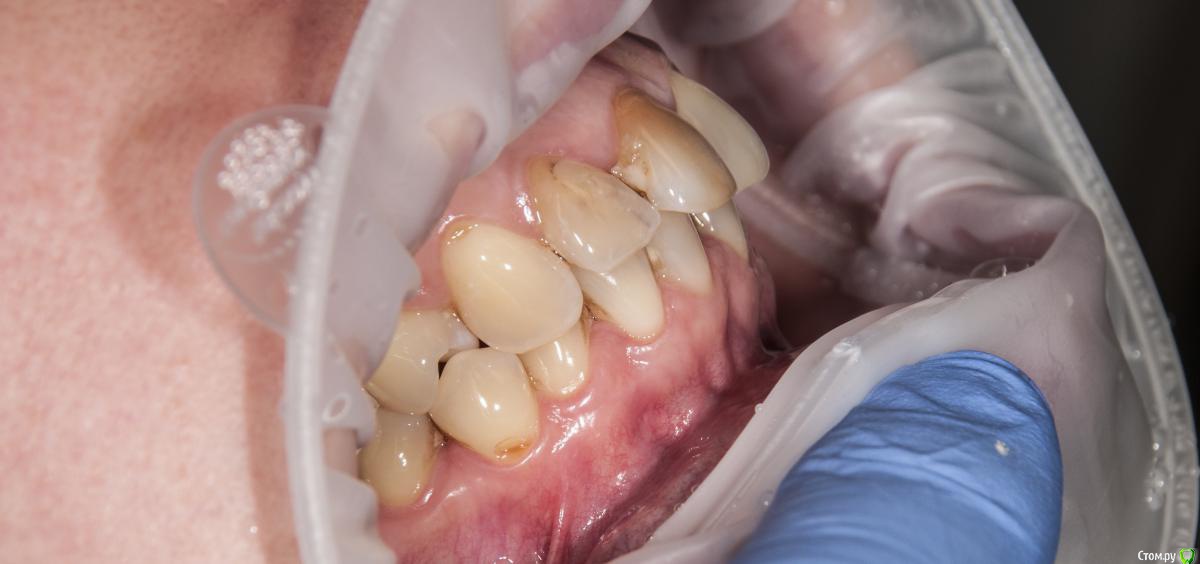

kamranchick Опубликовано 4 мая, 2018 Поделиться Опубликовано 4 мая, 2018 Добрый день Уважаемые коллеги, имеются проблемы с ортодонтией в нашем славном городе.Какие будут предложения по кейсу, сколько визитов и по ценникам, можно в личку.Пациент готов ездить в другие городаP.S пациент тоже будет следить за ходом этой ветки))) Ссылка на комментарий

krokomot Опубликовано 4 мая, 2018 Поделиться Опубликовано 4 мая, 2018 А импланты уже успели установить. 1 Ссылка на комментарий

kamranchick Опубликовано 4 мая, 2018 Автор Поделиться Опубликовано 4 мая, 2018 А импланты уже успели установить.Как видите вопросов много конечно, но что можно предложить имея такую картину. Ссылка на комментарий

krokomot Опубликовано 4 мая, 2018 Поделиться Опубликовано 4 мая, 2018 в данной ситуации конечно шляпа у пациента, если совсем все плохо, можно бы, ло бы просанировать для начала, снять скан, затем, поробовать на инвизилайнерах решить основные проблемы в окклюзии , затем тотальное протезирование. Идейка конечно не айс, но всё же выход. Ссылка на комментарий